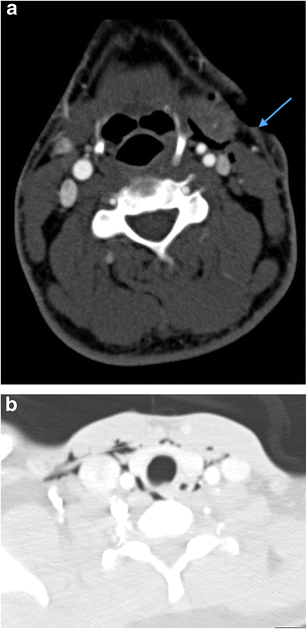

a Axial image of MDCTA of sharp (non-projectile) penetrating injury to the left zone 3. The implement bisected the left carotid sheath just below the skull base with the wound track (blue arrow) splaying the internal carotid artery (red arrowhead) from the internal jugular vein (blue arrowhead) but not causing any radiologically evident vascular injury. The patient exhibited clinical signs of Collet-Sicard syndrome—palsies of cranial nerves IX, X, XI and XII. The MDCTA demonstrates flattening of the left lateral pharyngeal recess (red arrow) compared with the contralateral side as a result of a combination of haematoma and superior pharyngeal constrictor paresis (the motor supply of the superior pharyngeal constrictor is through the motor component of the pharyngeal plexus derived from the cranial part of the accessory [XI] nerve). There is a nasogastric (NG) tube in situ. b Axial image of MDCTA of the same patient as in a showing evidence of left hypoglossal nerve palsy—there is flaccid prolapse of the tongue base (blue arrow) and deviation of the median fatty raphe to the ipsilateral side (blue arrowhead) and reduced calibre of the left glossopharyngeal sulcus (red arrow). The NG tube is noted in situ. c Axial image of MDCTA of same patient as in a and b. There is subtle medialisation of the left true vocal cord (blue arrow) consistent with a left vagus nerve palsy confirmed on flexible nasoendoscopy; this is one of the components of Collet-Sicard syndrome. The NG tube is evident in situ. d Coronal reformat of the same patient as in a, b and c. A metal fragment of the implement used to inflict the penetrating injury remains lodged in the left prevertebral soft tissues (blue arrow) having bisected the left carotid sheath and injured the adjacent cranial nerves